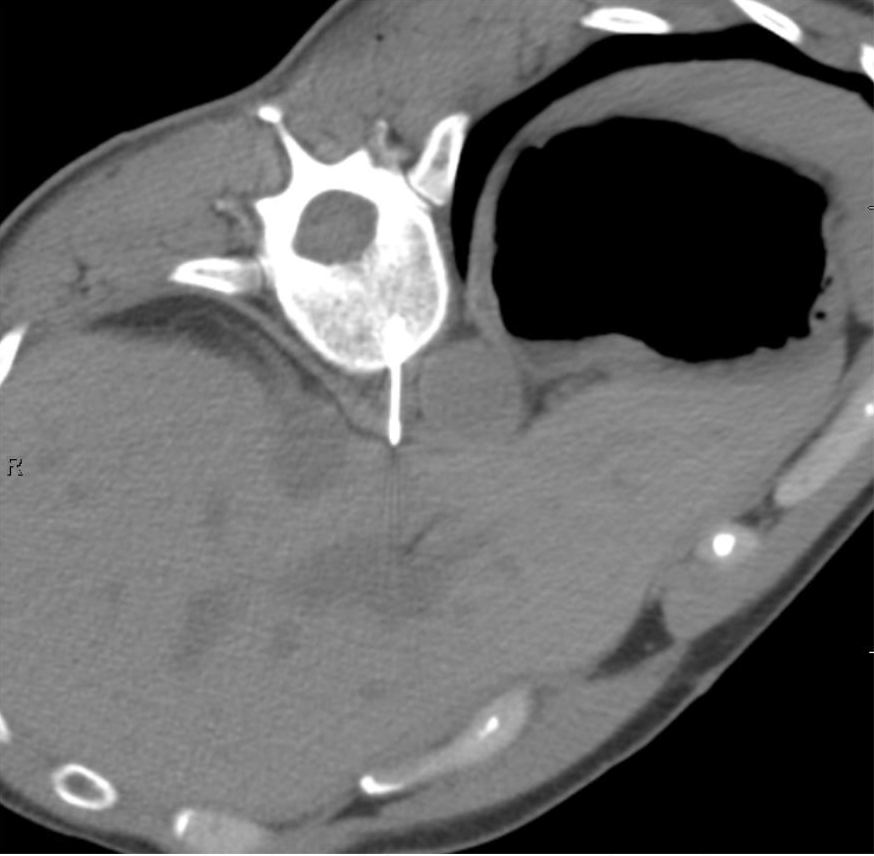

The location proved a challenge for access (Figure 1). The lesion was nestled anterior to the vertebral bone, and posterior to the liver and the aorta. There were no traditional percutaneous approaches that would guarantee access while maintaining safety. After a multidisciplinary discussion between medical oncology, radiation oncology, and interventional radiology, the decision was made to pursue a left transpedicular, transvertebral body approach. A biopsy would be performed and, if immediate assessment of the biopsy was positive for malignancy, cryoablation in the same session for immediate local tumor control.

FIGURE 2. Initial axial noncontrast CT image from day of procedure. A red arrow points to the right retrocrural lymph node lesion, nestled anterior to the vertebral bone, and posterior to the aorta and liver.